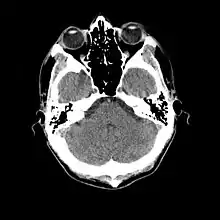

Brain endocasts

Normal human brain CT scan

A brain endocast is the imprintation of the inner features of a cranium that captures the details created from pressure exerted on the skull by the brain itself. Endocasts can be formed naturally by sedimentation through the cranial foramina which becomes rock-hard due to calcium deposition over time, or artificially by creating a mold from silicon or latex that is then filled with plaster-of-Paris while sitting in a water bath to equalize forces and retain the original shape. Natural endocasts are very rare; most of those that are studied are the result of artificial methods. Although the name implies that it is a copy of the once living brain, endocasts rarely exhibit convolutions due to buffering by the pia mater, arachnoid mater, and dura mater that once surrounded and protected the brain tissue. Furthermore, not all endocasts are created from a complete cranial fossil and subsequently, the missing parts are approximated based on similar fossils. In some cases, fragments from several fossils of the same species are used to construct a single endocast.[7]

More recently, computed tomography has played a large role in reconstructing endocasts. The procedure is non-invasive and has the advantage of being able to analyze a fossil in record time with little risk of damaging the fossil under review. CT imaging is achieved through the application of x-rays to produce tomographs, or sectional density images, which are similar to the images produced during MRI scans.[8] CT scans use slices approximately 1 mm thick to reconstruct a virtual model of the specimen.[9] This method is especially useful when a fossil cranium is occupied by a natural endocast that cannot be removed without destroying the skeletal portions of the fossil. Because the cranium and its contents are of different densities, the endocranial cavity and its unique traits can be reconstructed virtually.[8]

Radiographic technique such as computed tomographic imaging, or CT scans, coupled with computer programming have been used to analyze brain endocasts from as early as 1906.[10] Recent development of advanced computer graphics technology have allowed scientists to more accurately analyze of brain endocasts. M. Vannier and G. Conroy of Washington University School of Medicine have developed a system that images and analyzes surface morphologies in 3D. Scientists are able to encode surface landmarks that allows them to analyze sulcal length, cortical asymmetries and volume.[11] Radiologist, paleoanthropologists, computer scientists in both the United States and Europe have collaborated to study such fossils using virtual techniques.[10]